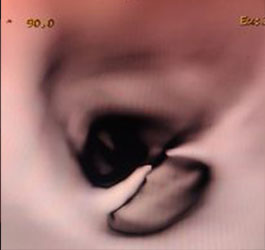

Virtual Bronchoscopy

Bronchoscopy : Black Hole sign